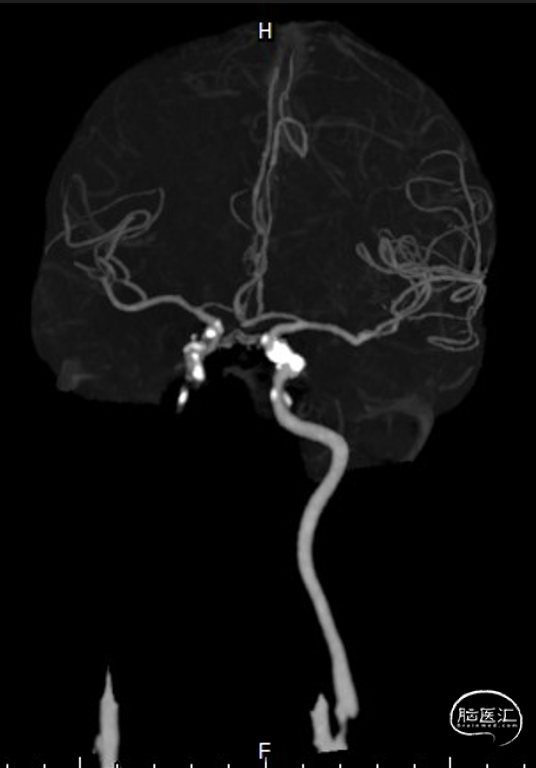

头颈部CTA

DSA

复查造影支架成形良好,颅内较前无明显改变,未发现血管减少影像,供血较前明显改善。